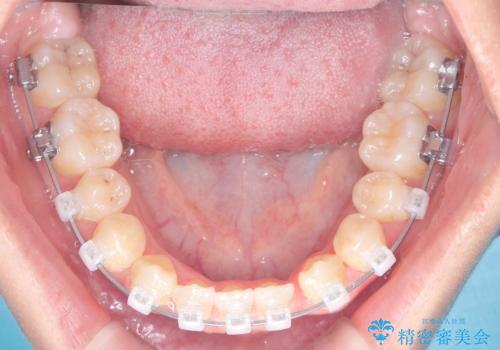

安全かつ確実に抜歯スペースを閉じ、咬み合わせを完成させるため、マウスピースから**ワイヤー矯正(マルチブラケット装置)**へ切り替えるリカバリープランを提案しました。

装置の変更と歯肉への配慮: ワイヤー矯正は歯の根(歯根)を平行に移動させる「歯体移動」を得意としています。本症例では、歯肉退縮を防ぐために、歯の傾きを精密にコントロールしながら抜歯スペースを閉じる必要がありました。ワイヤー装置を用いることで、インビザラインでは難しくなっていた三次元的な細かい調整を可能にしました。